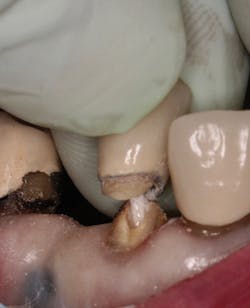

Figure 1: Occlusal image of finished root canal prep after gutta-percha removal

The root canal on No. 10 was completed using the WaveOne Gold system (Dentsply Sirona). Upon completed obturation, care was taken to remove only excess gutta percha from the canal using a warmed endodontic plugger. Removal extended approximately 4 mm to 5 mm into the canal space (figure 1).